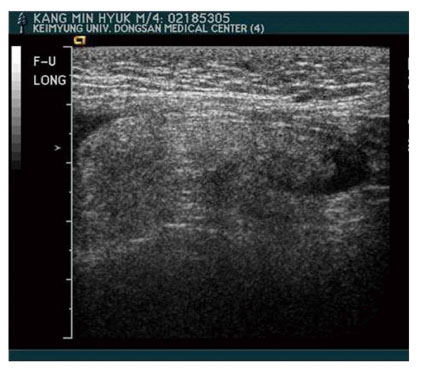

th day of post appendectomy and worsened steadily. On physical examination, asymmetrical swelling without redness on the right groin in the pubic region and mild scrotal swelling were observed with palpable thickened spermatic cord. Neither tenderness or rebound tenderness were noted. Ultrasonography showed an apparent right inguinal hernia containing omental fat (

Fig. 1Ultrasonography showed omental fat containing hernia sac.